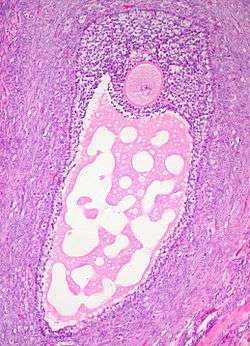

![]() Histology section of a mature ovarian follicle. The oocyte is the large, round, pink-staining cell at top center of the image. | |

Ovarian follicles are the basic units of female reproductive biology. Each of them contains a single oocyte (immature ovum or egg cell). These structures are periodically initiated to grow and develop, culminating in ovulation of usually a single competent oocyte in humans.[3] They also consist of granulosa cells and theca of follicle.

The granulosa cells, in turn, are enclosed in a thin layer of extracellular matrix – the follicular basement membrane or basal lamina (fibro-vascular coat in picture). Outside the basal lamina, the layers theca interna and theca externa are found.